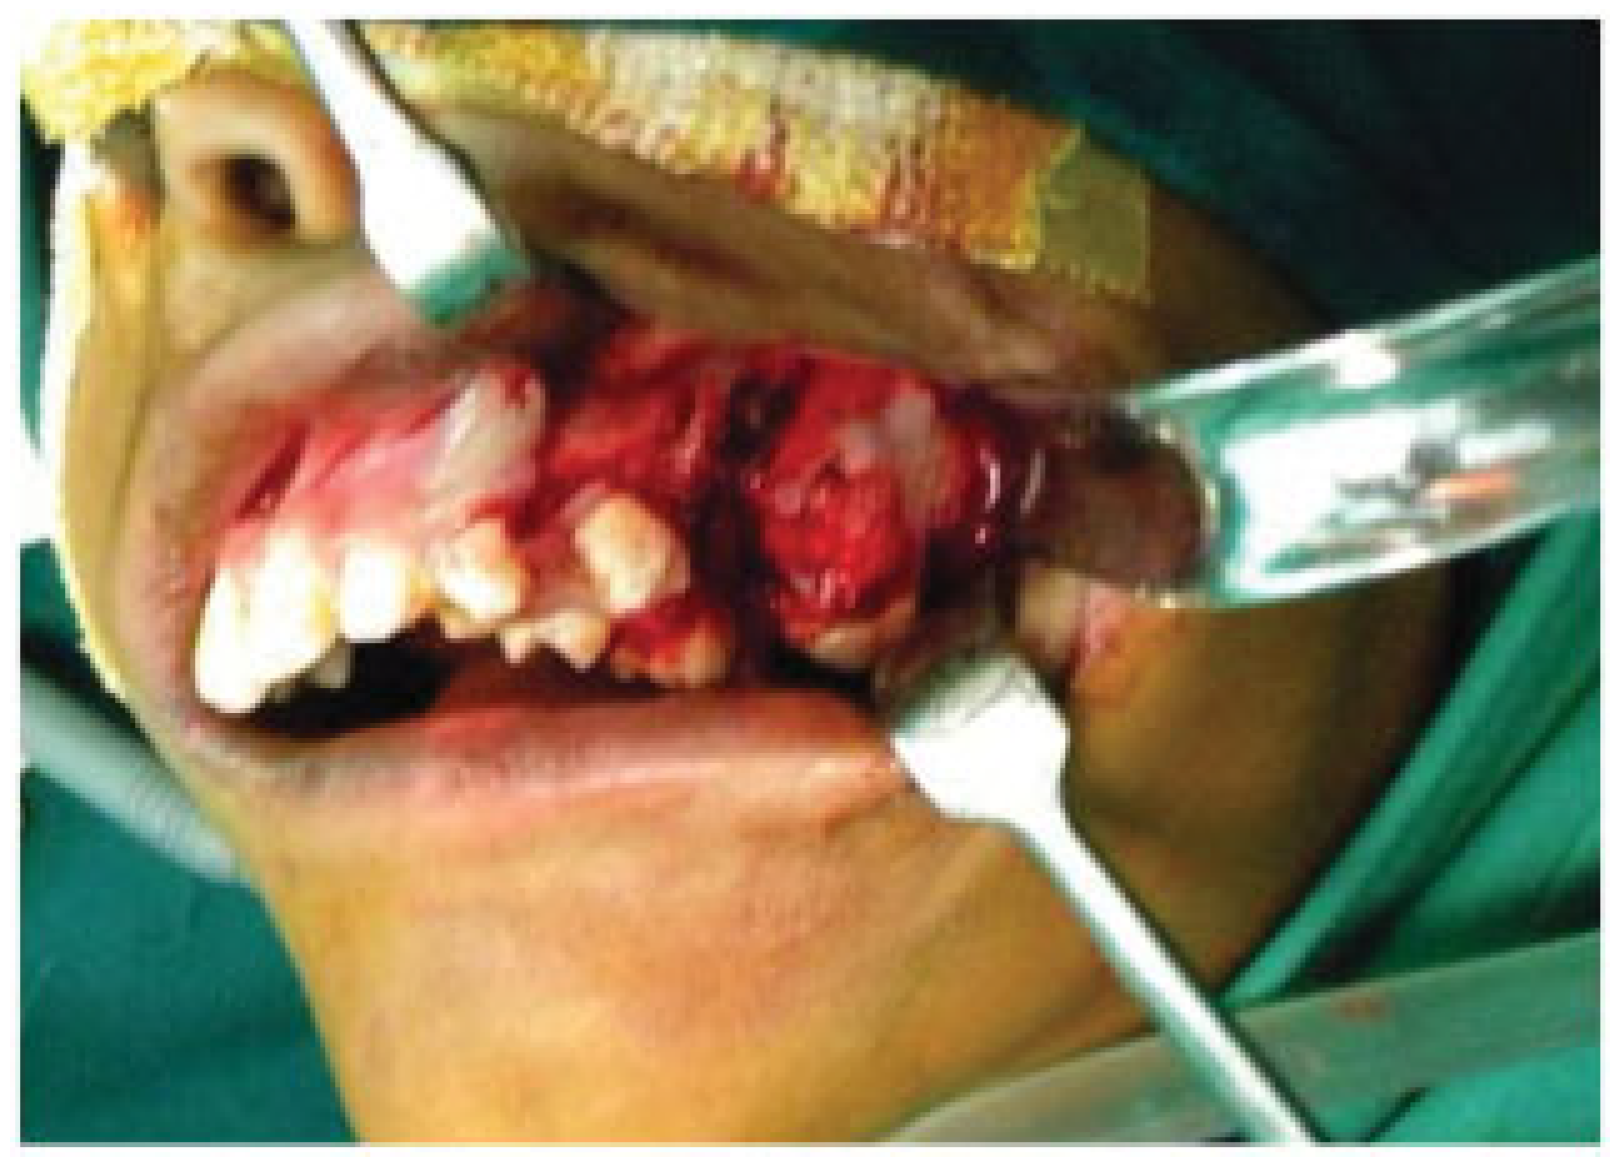

A Rare Case of Multiple Oblique Facial Clefts with Supernumerary Teeth: Case Report

- Incomplete Tessier 7 soft tissue facial cleft and a complete skeletal Tessier 7 cleft on the right side

- Incomplete Tessier 5 skeletal and soft tissue Tessier 6 facial cleft on the left side